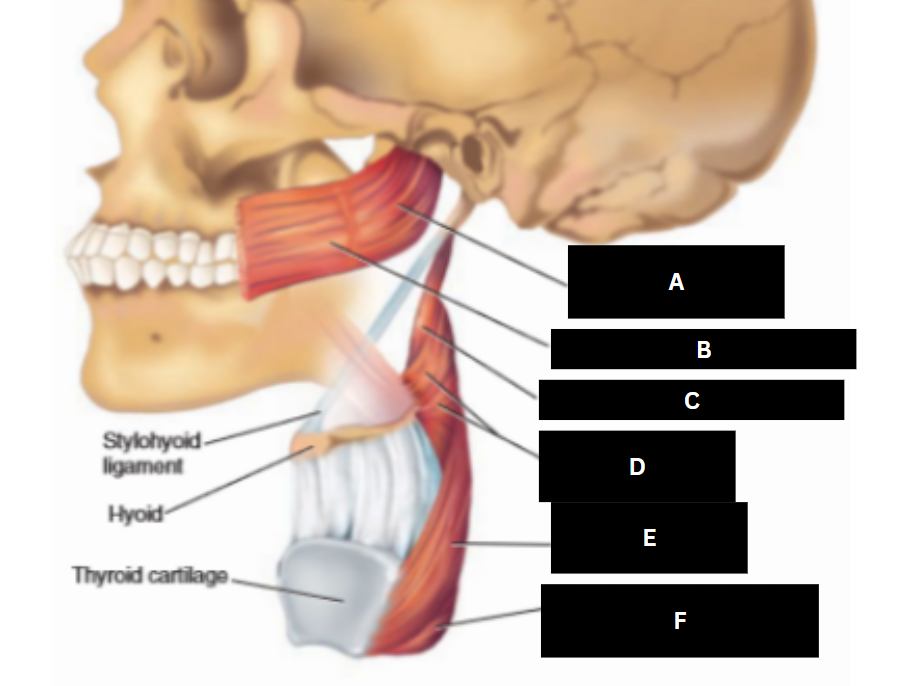

Stylopharyngeus

A

Styloglossus

B

Stylohyoid

C

Cricopharyngeus

D

Superior pharyngeal constrictor

E

Middle pharyngeal constrictor

F

Pharyngeal raphe

G

Inferior pharyngeal constrictor

H